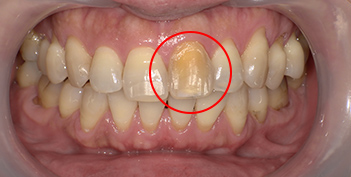

インターナルブリーチの治療例

インターナルブリーチとは、一般的に神経の死んでいる歯を専用の漂白剤を注入・洗浄することで白くする方法です。

- 50代 女性

| 年齢/性別 | 50代 女性 |

|---|---|

| 施術回数 | 3回 |

| 費用 | 50,000円(税抜) |